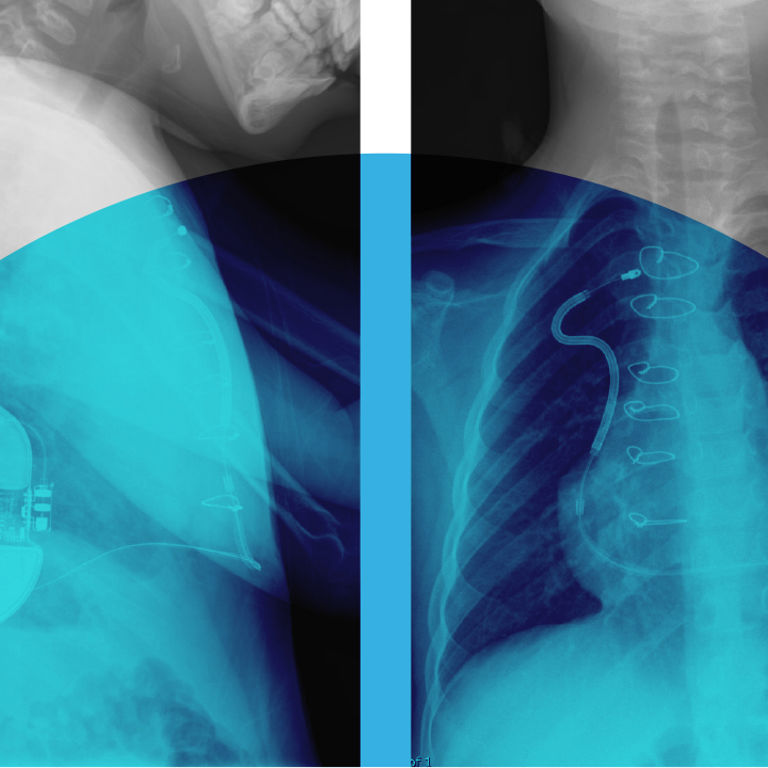

X-ray of S-ICD